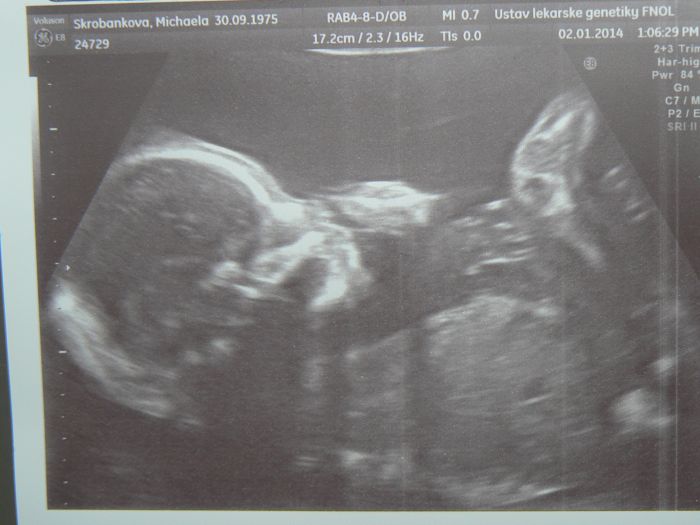

Mickey, tak to jsou krasne zpravy z UZ.